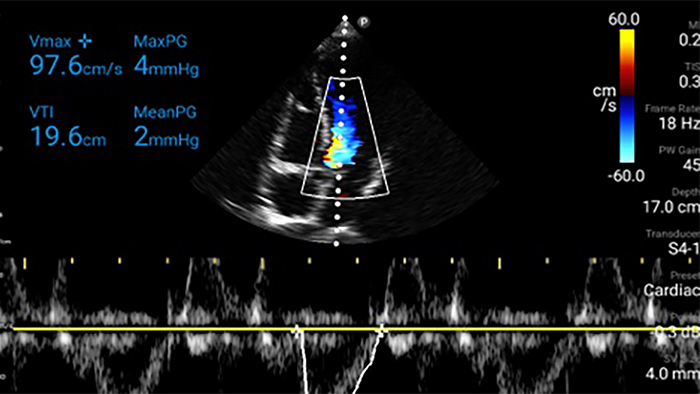

Actúe más rápido para proteger el corazón de sus pacientes

Cuando los segundos cuentan, el ultrasonido portátil puede marcar la diferencia. Lumify puede proporcionar las imágenes de alta definición que requiere cuando y donde las necesite.

Oportunidad de revertir potencialmente la miocardiopatía

Introducción a la ecocardiografía transtorácica